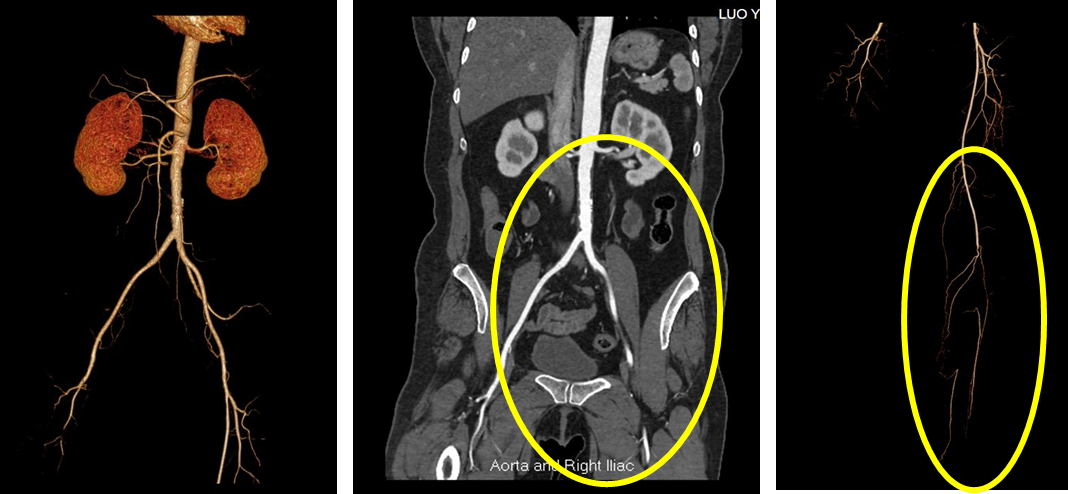

术前CTA

手术:

1. 切开暴露血管

2. 造影明确病灶

3. 导管取栓

4. 置管药物灌注

5. 全程造影

远端输出道欠佳,调整药物治疗方案

系统应用尿激酶原、前列地尔溶栓及活血、扩管药物应用

改抗凝(低分子肝素6000u Q12H)为肝素钠25000u/日(2支)

单抗血小板(阿司匹林)、调脂